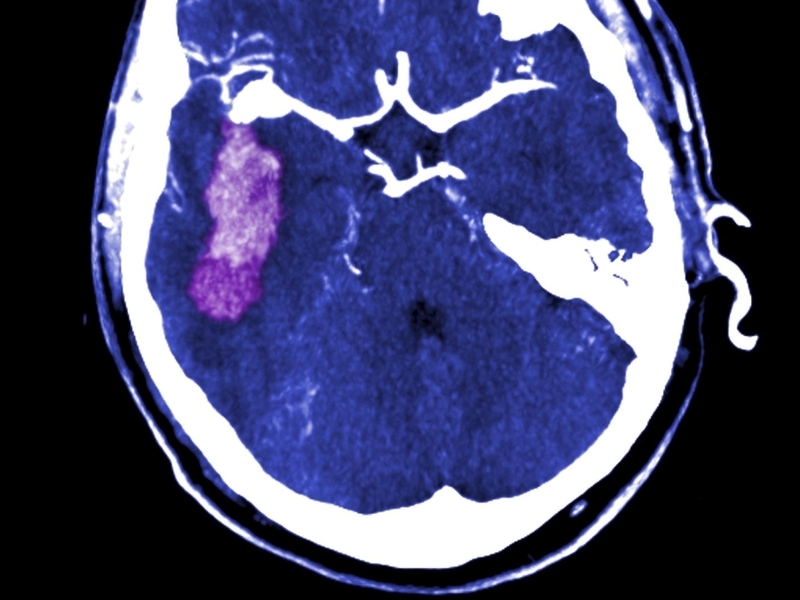

Stroke - Report on cardiovascular services

Cardiovascular diseases and conditions are the biggest killer in Ireland each year, claiming over 10,000 lives.